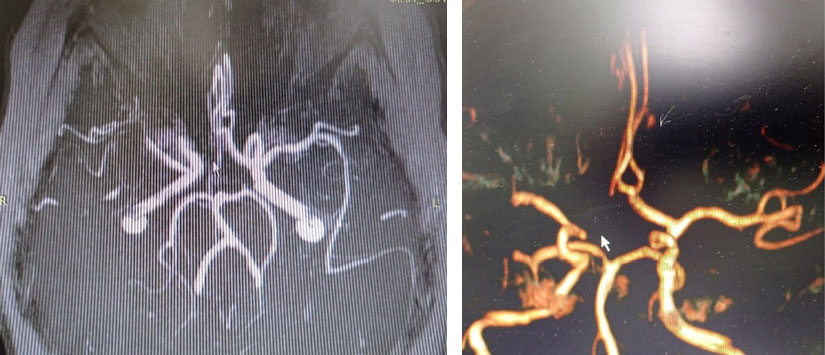

Данные магнитно-резонансной томографии пациентов с этими видами патологии представлены на рис. 1 и 2.

Рис. 1. Пациент В., передняя трифуркация левой внутренней сонной артерии, магнитно-резонансный сигнал от правой задней соединительной артерии отсутствует, низкоинтенсивный сигнал от правой передней мозговой артерии

Рис. 2. Пациент В., очаг ишемии в области моста (вертебробазилярный бассейн)